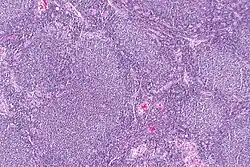

Dysgerminoma | Dysgerminoma characterized by uniform cells resembling primordial germ cells separated by fibrous septa with lymphocytes. | Category: Histopathology of ovarian dysgerminoma | Ovarian dysgerminoma |

![]() |